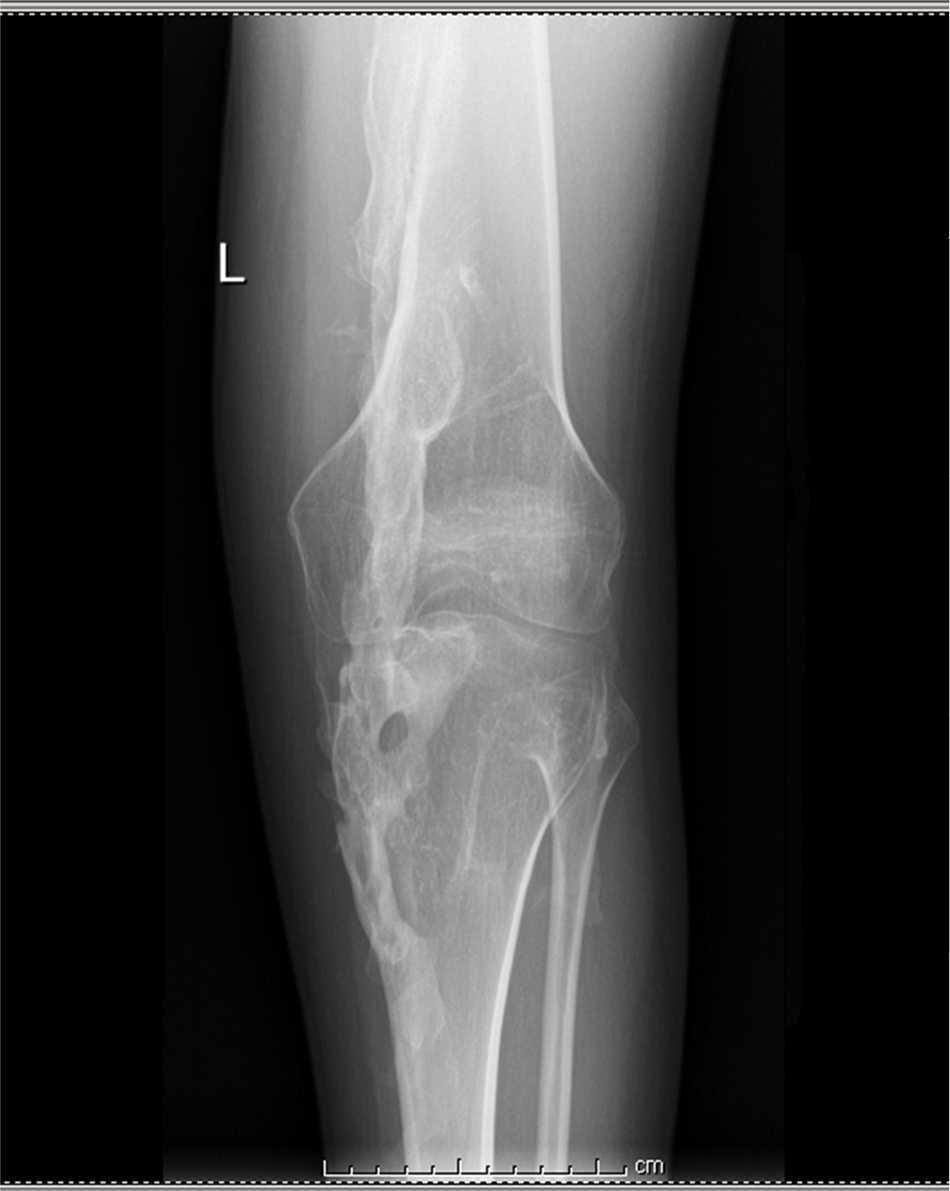

Puentes óseos formados desde el tercio proximal del humero hacia la